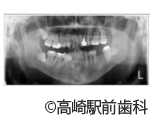

【症例1】50代男性 左奥歯の切らない縫わないインプラント

- 治療前

- 治療中

- 治療後

- 治療名

- 左奥歯の切らない縫わないインプラント

- 費用

- 308,000円(税込10%)

- 期間

- 1ヵ月半

- 患者様

- 男性

治療内容

患者様の症状

左奥歯に歯が無い状態でした。

治療法

普通、インプラント手術は歯肉を大きく切開と剥離しますが、当院で対応可能な切らない縫わないインプラント治療(フラップレス手術)の場合、小さな穴を開けてインプラントを埋めるので、無切開、無剥離で行うことが可能です(こちらが術中の写真です)。

これによって術後の腫れ、出血、痛みをかなり軽減でき治療期間も短くなります。縫わないので当然、抜糸も不要です。フラップレス手術は誰にでも必ずできるわけではありませんが、当院では多くの方が埋入時にフラップレス手術を行っており、身体的負担の少ない治療を受けています。 -

治療結果

歯肉を切開せず、インプラントを埋入することができました。

※治療結果は患者様によって個人差があります。